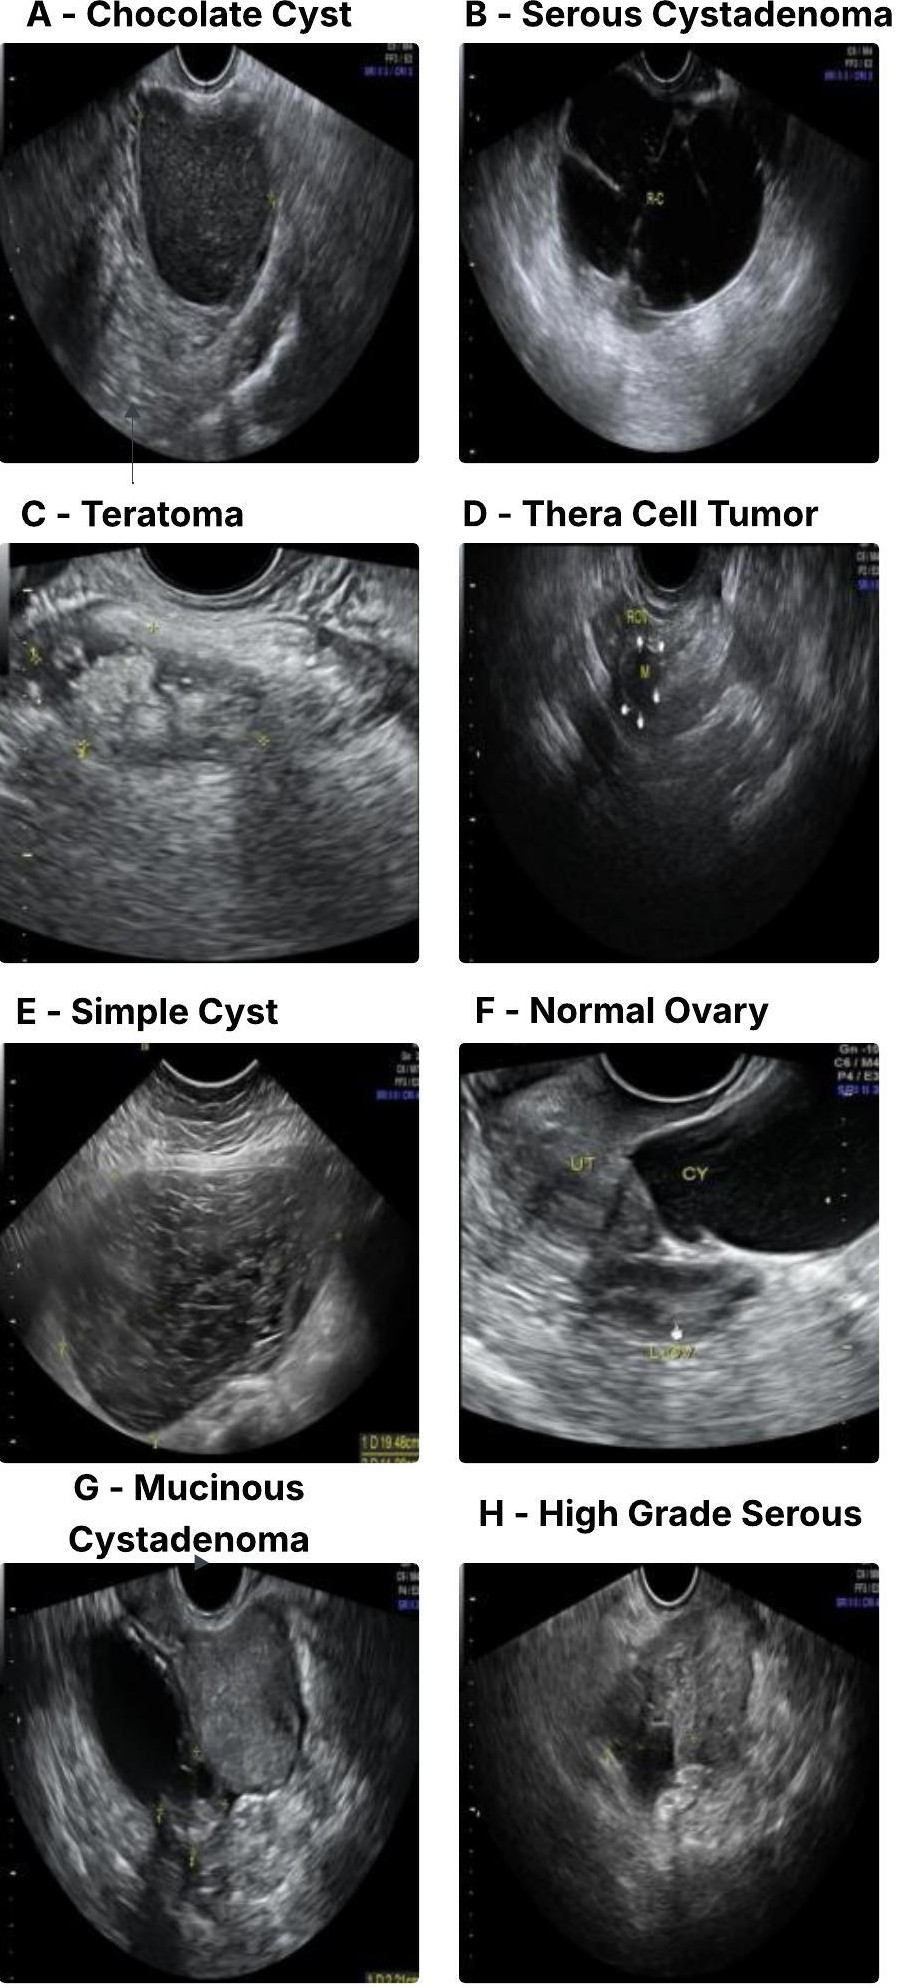

2) Ovarian Tumors (MMOTU-2D). The MMOTU-2D dataset [17] consists of 1469 2D ovarian tumor US images from 247 patients, annotated into eight distinct pathological subtypes (chocolate cyst, serous cystadenoma, teratoma, thera cell tumour, simple cyst, normal ovary, mucinous cystadenoma, high grade serous), as seen in Fig. 6. We followed the official split of 1000 images for training and 469 for validation provided by the dataset authors [17]. The multi-class classification scheme on this dataset evaluates the capacity of the USF-MAE model to differentiate among multiple tumour types that have different appearances. The dataset’s clinical application is significant, as accurate identification of the ovarian tumor subtypes is crucial to the planning of treatments. This dataset is a valuable resource for evaluating the performance of specific subtypes of ovarian tumours.

Refer to caption

Figure 6: US images of various ovarian lesions, including entities such as Chocolate Cyst (A), Serous Cystadenoma (B), Teratoma (C), Thera Cell Tumor (D), Simple Cyst (E), Normal Ovary (F), Mucinous Cystadenoma (G), and High Grade Serous (H) from the MMOTU-2D dataset.